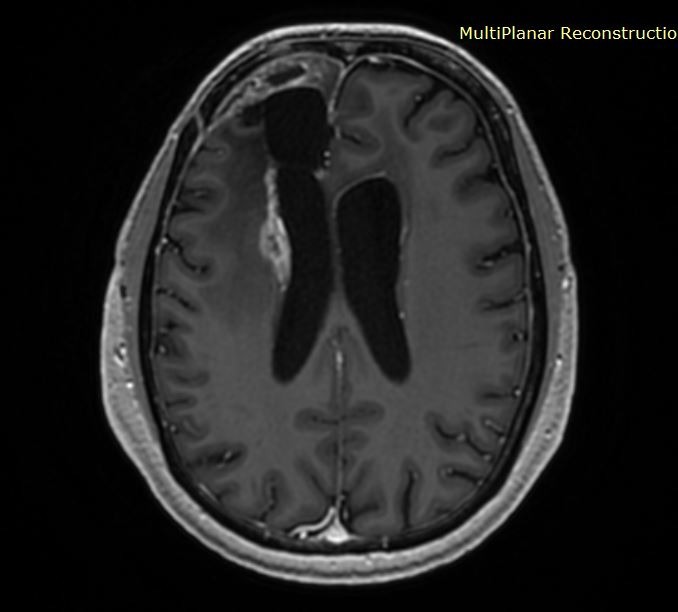

Ασθενής με ιστορικό χειρουργηθέντος γλοιοβλαστώματος παρουσίασε, στις μαγνητικές τομογραφίες παρακολούθησης, την εμφάνιση μιας νέας βλάβης ύποπτης για υποτροπή, η οποία παρουσίαζε σταδιακή αύξηση μεγέθους.

Η βλάβη εντοπιζόταν εν τω βάθει, δηλαδή σε σχετικά βαθιά περιοχή του εγκεφάλου. Με τον ασθενή συζητήθηκαν αναλυτικά οι διαθέσιμες θεραπευτικές επιλογές: είτε νέα κρανιοτομία με αφαίρεση της βλάβης είτε εξάχνωση (καταστροφή) της νέας εστίας με τη χρήση λέιζερ.

Αρχικά, συχνά δεν είναι βέβαιο αν πρόκειται πράγματι για υποτροπή, δηλαδή για επανεμφάνιση του όγκου ή αν πρόκειται για μεταθεραπευτικές αλλοιώσεις (δηλ. αλλοιώσεις στη μαγνητική οι οποίες οφείλονται στο χειρουργείο ή στην ακτινοβολία).

Επίσης, συχνά οι υποτροπές είναι σε σημεία του εγκεφάλου που είναι βαθιά και οι ασθενείς είναι ήδη επιβαρυμένοι από τις ως τώρα θεραπείες.

Στην προκειμένη περίπτωση η βλάβη καταστράφηκε πλήρως.